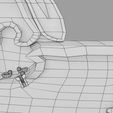

神经肌肉接头示意图